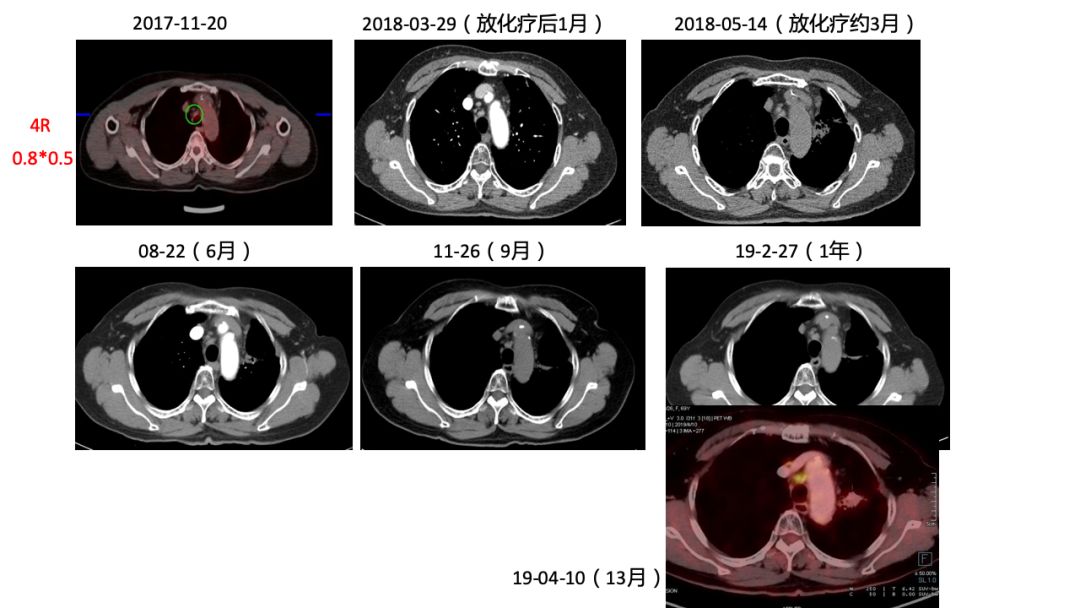

2)患者2017年11月因晨起咯血丝痰在外院行CT提示肺部肿物,考虑肺癌,后于2017-11-20我院行PET-CT,提示左肺下叶肿块,纵隔8L组淋巴结肿大,糖代谢增高,考虑左肺下叶中央型肺癌并纵隔淋巴结转移;左肺下叶阻塞性炎症。

2018-01-11开始行同步放化疗,放疗予以IMRT 60Gy/30F,化疗予以EP方案同步2周期。

3)原发灶+8组LN(放疗区) PR 疗效。

5)4R,10R组LN(非放疗区)1年来随访大小未见变化,4R实性程度增高,代谢增高2倍。